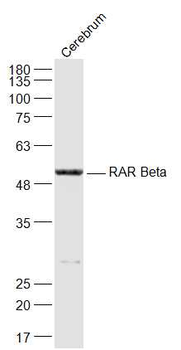

RARB Rabbit Polyclonal Antibody [orb11327]

FC, ICC, IF, IHC-Fr, IHC-P, WB

Bovine, Canine, Gallus, Porcine, Rat

Human, Mouse

Rabbit

Polyclonal

Unconjugated

50 μl, 100 μl, 200 μlTIG2 Rabbit Polyclonal Antibody [orb11481]